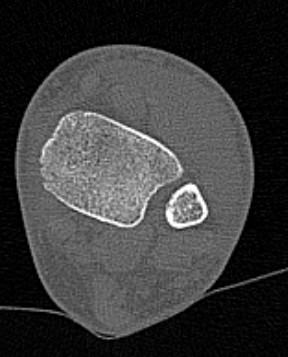

Во время исследования рентгеновская трубка томографа вращается вокруг исследуемой области и производит множество послойных снимков с шагом от 0,5 мм. Полученные снимки поперечного сечения с помощью компьютерной программы могут быть преобразованы в 3D-изображения исследуемого органа. Это позволяет выявлять различные патологические процессы на начальных стадиях и назначать своевременное лечение.

За счет быстроты, доступности и неинвазивности (то есть исследование не требует вмешательства в организм) метод КТ особенно востребован в ортопедии и травматологии. Мультиспиральная КТ лучше всего визуализирует плотные ткани, такие как кости и хрящи. Поэтому, в первую очередь, применяется для диагностики травм суставов (вывихов, подвывихов, переломов).

В отличие от обычного рентгена, при котором изображения костных структур накладываются друг на друга, что затрудняет диагностику, компьютерная томография дает возможность увидеть объемную модель сустава, наглядно оценить пространственное соотношение внутрисуставных структур, суставных поверхностей, расположение костных отломков при переломах и травмах. Это особенно важно в ходе подготовки к оперативному вмешательству и в послеоперационном периоде для оценки успешности проведенной операции.